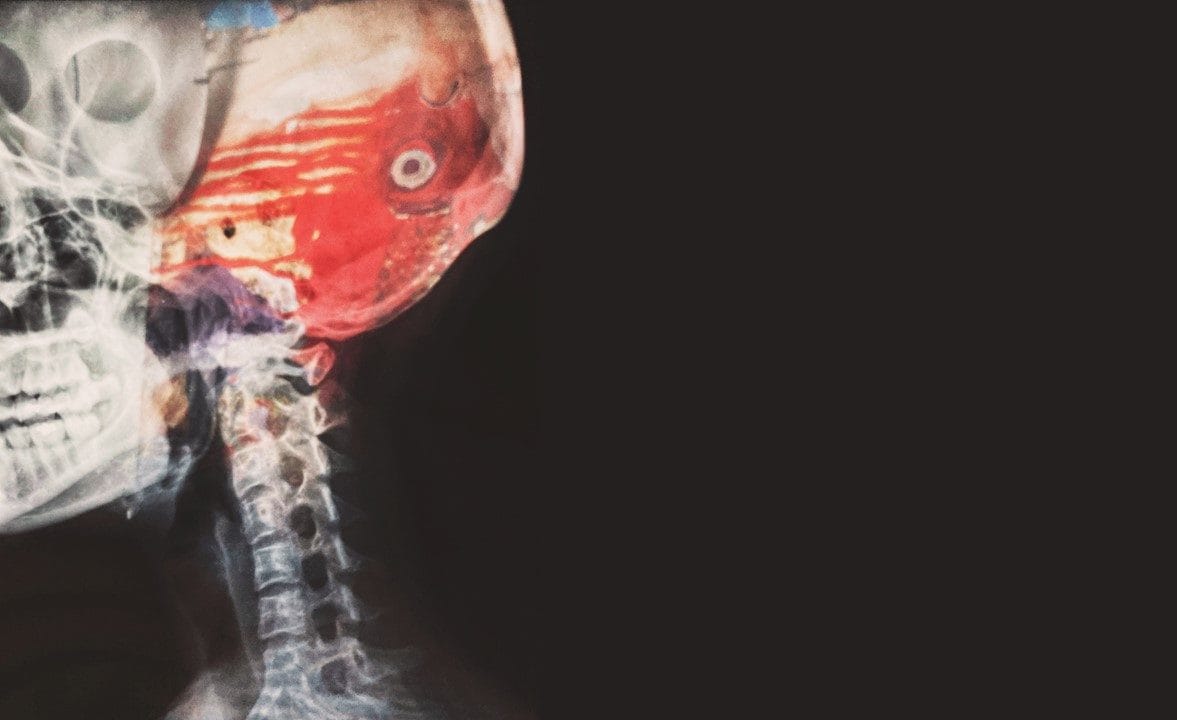

腦血管主要的疾病分為「腦缺血(cerebral ischemia)」和「腦出血(cerebral hemorrhage)」 二種。這二者都是腦部正常的血液循還被破壞,造成腦部的氧氣和能量供應不足,使得腦細胞無法正常新陳代謝。

腦組織缺氧就會壞死,腦功能也會逐漸隨之喪失。患者會在症狀上呈現意識和運動的嚴重停滯或障礙,也就是一般所稱的「腦中風(Stroke)」。 中風是因為通往大腦的血流受到干擾,導致大腦組織和功能受損。 中風後的復健和治療,也因損害的腦區不同而有差異。

出血型中風,通常是因為腦中的血管破裂,導致出血所造成。高血壓容易讓血管受壓破裂,是一個重要的危險因子;因此當發生出血型腦中風時,需要立即進行止血手術。

腦血管破裂時,通常病情發展很快,並且會伴隨激烈疼痛以及意識不清的情況,甚至造成動作困難或昏迷。